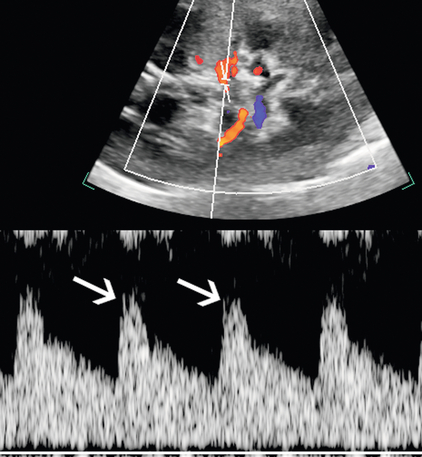

Косвенный метод оценки сигналов сегментарных почечных артерий по РАС становится важным, когда всю длину главной почечной артерии невозможно непосредственно увидеть с помощью ультразвука. Ставрос и др.5 , предположили, что нормальная морфология внутрипочечной волны с ранним систолическим пиком в верхних, межполярных и нижних полюсных сегментарных почечных артериях может использоваться для адекватного исключения значимого РАС. Этот нормальный пик податливости ( рис. 9-14 ) отсутствует при стенозе, ограничивающем поток в проксимальной артерии, хотя другие считают этот признак менее чувствительным.

РИСУНОК 9-14. Пик податливости нормальной сегментарной артерии. Дуплексная допплерография показывает небольшой ранний систолический пик (стрелки) в точке пиковой систолической скорости при отсутствии стеноза в восходящем направлении.

Еще одним критерием РАС является длительное время разгона более 0,07 секунды. Время ускорения – это временной интервал от начала систолы до раннего систолического пика. При притупленных формах сигналов этот ранний пик может отсутствовать, и измерение должно продолжаться от начала систолы до первой точки отклонения. Наличие морфологии волны тардус-парвус помогает в диагностике тяжелой формы РАС; однако его отсутствие не исключает РАС.Спектральная форма волны тардус-парвус определяется медленным подъемом вверх (тардус) и расширением спектра с притуплением систолического пика (парвус) ( рис. 9-15 ). Важно отметить, что у пациентов с атеросклеротическим заболеванием податливость сосудов может быть снижена, что делает морфологию волны тардус-парвус менее очевидной.

РИСУНОК 9-15. Стеноз почечной артерии. При дуплексной допплерографии сегментарной артерии нижнего полюса задержанное систолическое ускорение (тардус) и малая форма волны (парвус) соответствуют стенозу верхнего отдела, и необходима дальнейшая оценка главной почечной артерии, если стеноз еще не был непосредственно визуализирован.